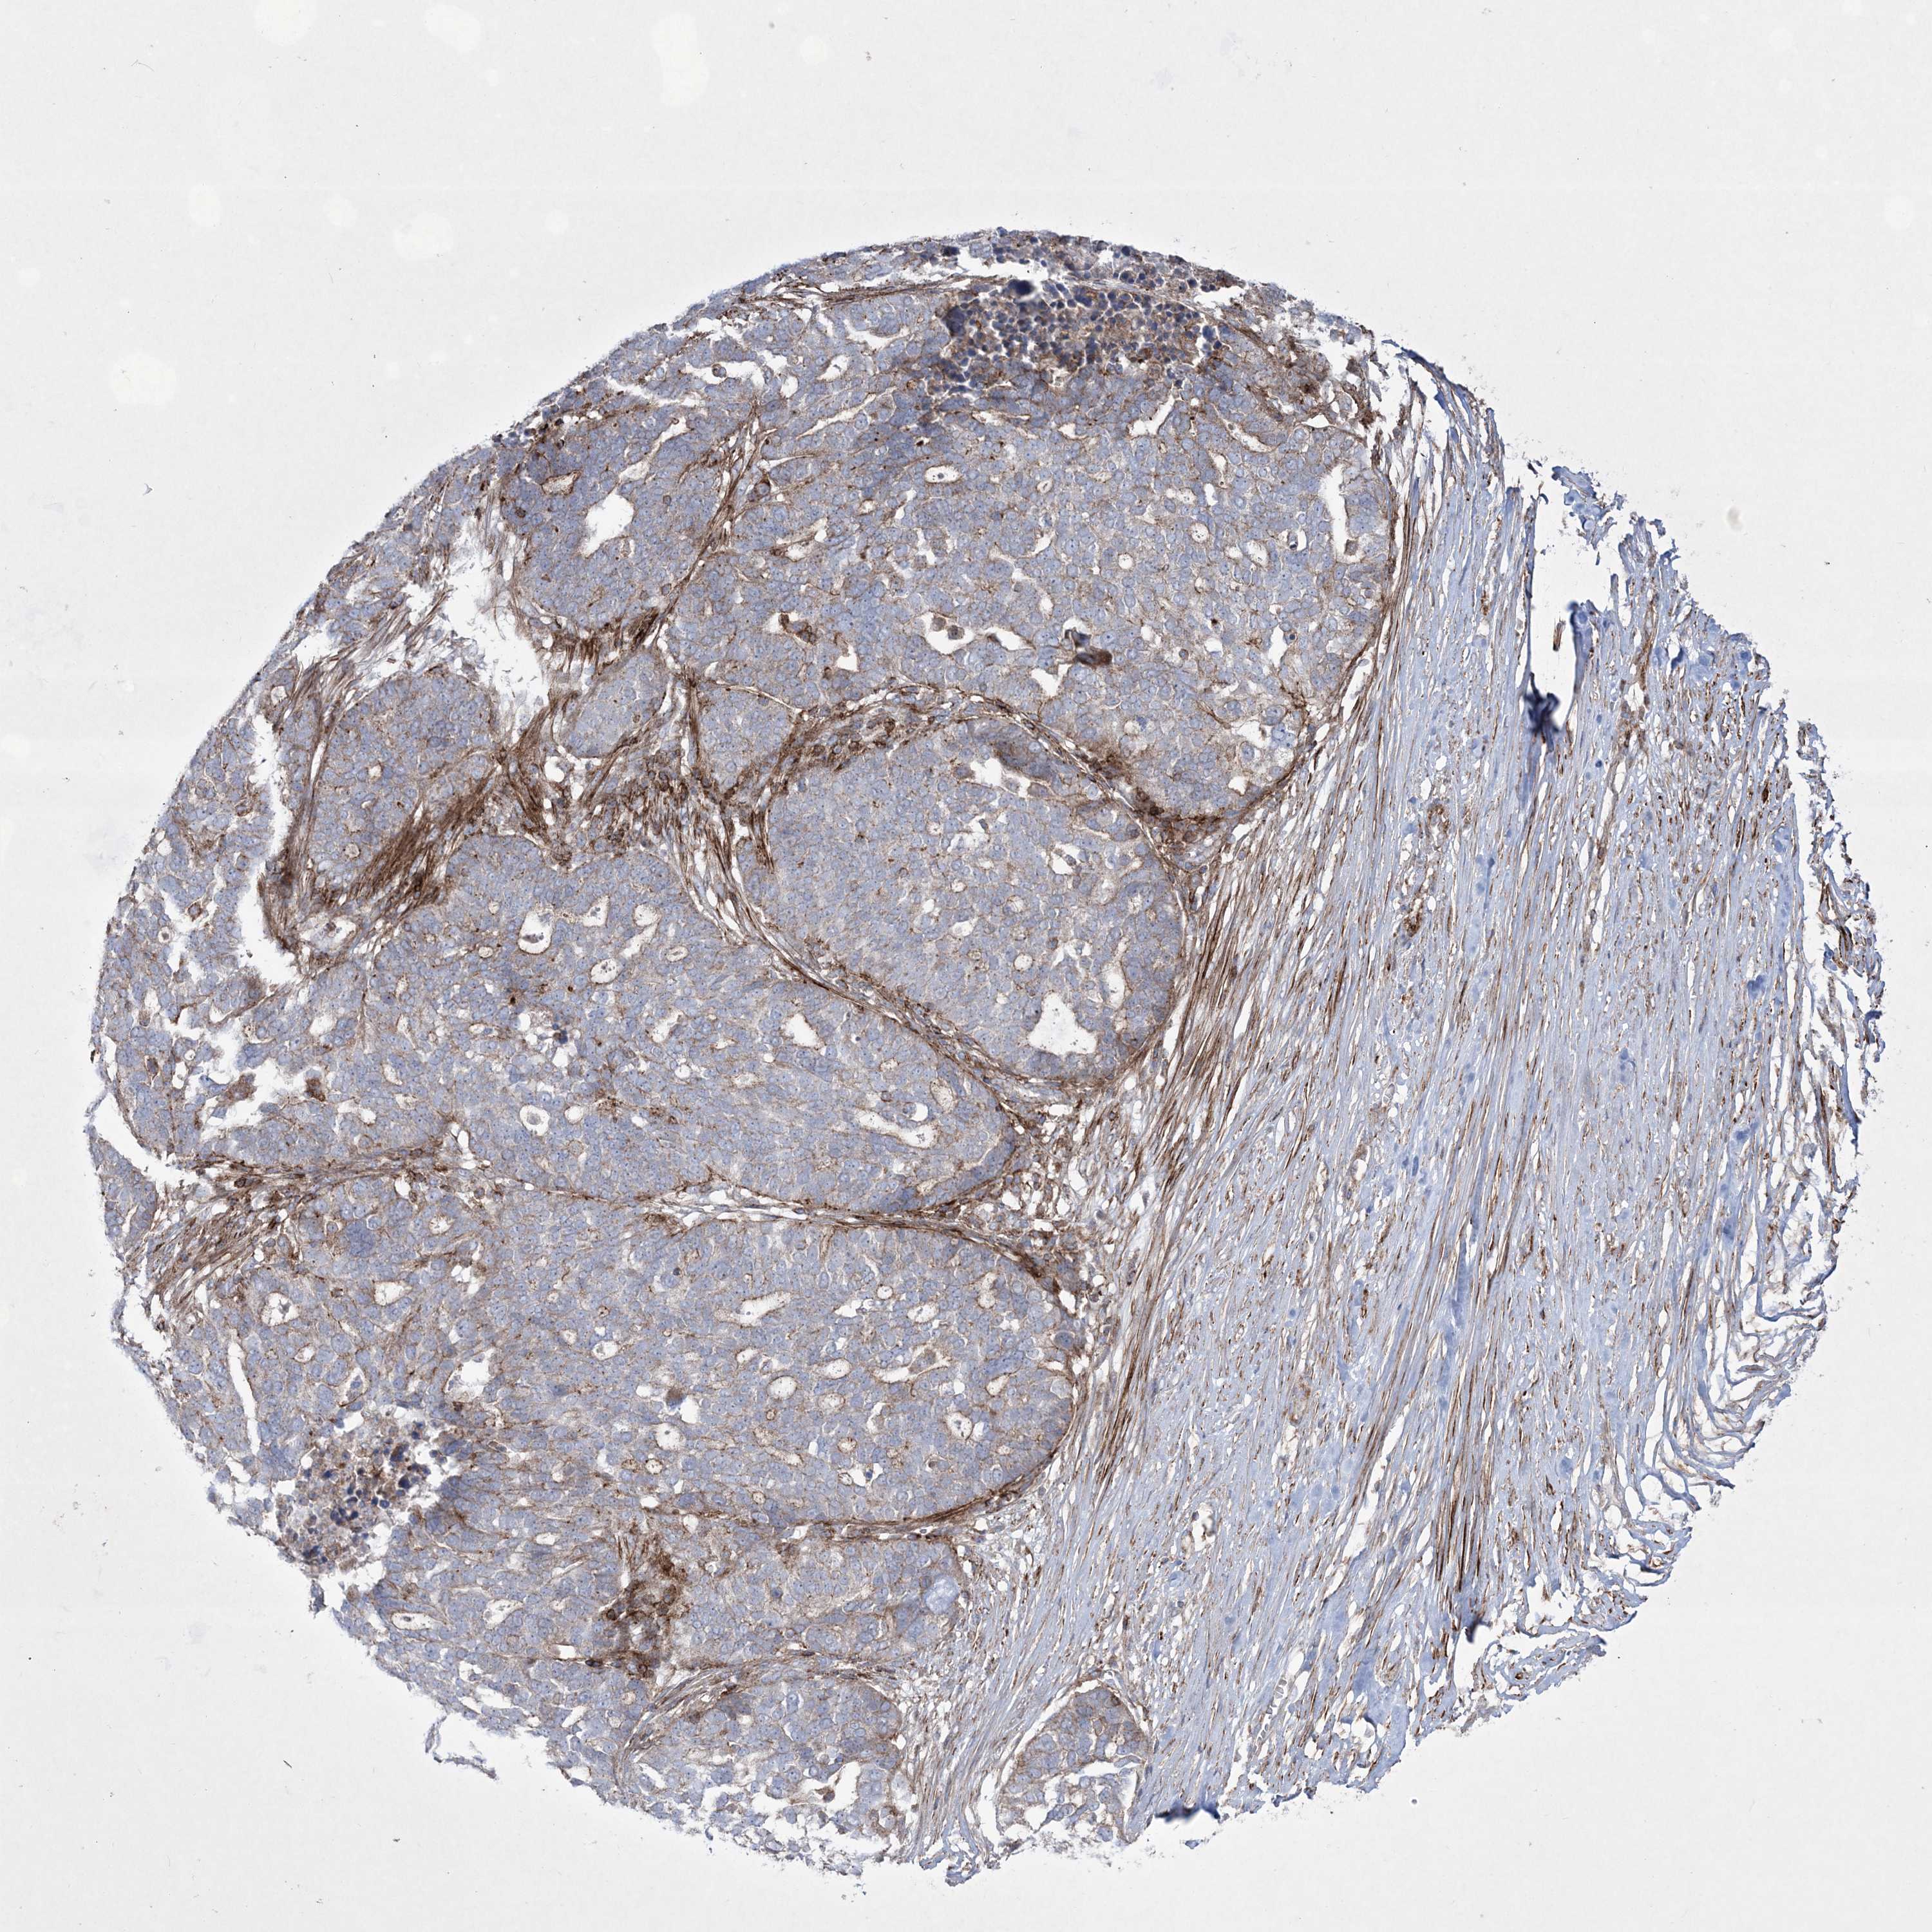

OVARIAN CANCER - Protein expressioni

A mouse-over function shows sample information and annotation data. Click on an image to view it in a full screen mode. Samples can be filtered based on level of antibody staining by selecting one or several of the following categories: high, medium, low and not detected. The assay and annotation is described here.

Note that samples used for immunohistochemistry by the Human Protein Atlas do not correspond to samples in the TCGA dataset.

Antibody stainingi

Antibody staining in the annotated cell types in the current human tissue is reported as not detected, low, medium, or high, based on conventional immunohistochemistry profiling in selected tissues. This score is based on the combination of the staining intensity and fraction of stained cells.

Each image is clickable and will lead to virtual microscopy that enables deeper exploration of all samples and also displays staining intensity scores, fraction scores and subcellular localization as well as patient and tissue information for each sample.

Antibody HPA037802

Antibody HPA037803

Cystadenocarcinoma, serous, NOS

Carcinoma, endometroid

Cystadenocarcinoma, mucinous, NOS

Carcinoma, NOS